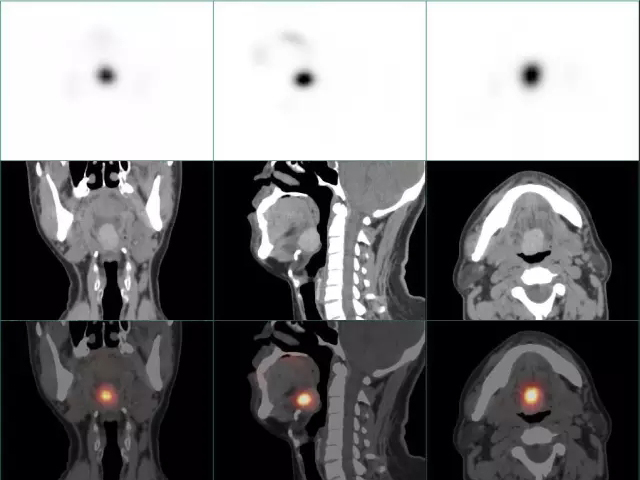

甲状腺显像结合颈部SPECT/CT断层显像融合特异性显示异位甲状腺 |